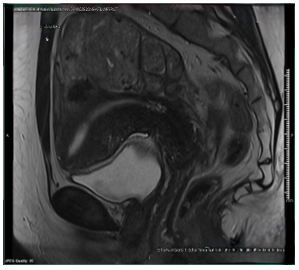

Intravenous Leiomyomatosis, Case Report and Literature Review

Manal Shaker Taha, Abdulmuiz Idrees, Ahmed Mahmoud, Reda Yousef, Helen Frise, Islam Abdulrahman, Manal Elbadrawy and Kerryn Lutchman Singh. 13(11): 01-04.